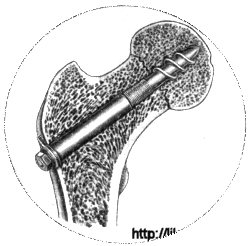

¨   Кортикальный остеосинтез(трехлопастной гвоздь, спицы, винты-фиксаторы Чарнлея, Скальетти, Чаклина, Родина и др.,)

При варусных невколоченных переломах шейки бедра наиболее рационально хирургическое вмешательство.

Существует два основных метода остеосинтеза медиальных переломов шейки бедра: 1) закрытый (внесуставной), когда сустав не вскрывают и место перелома не обнажают; 2) открытый (внутрисуставной) применяемый только в тех случаях, когда закрытая репозиция невозможна (чаще всего при интерпозиции капсулой и при старых переломах). Если рентгенологический контроль за положением отломков и фиксатора во время операции невозможен, также показан открытый остеосинтез. Закрытый остеосинтез проводят под местной анестезией или под наркозом после закрытой репозиции скелетным вытяжением или после одномоментной репозиции на ортопедической столе.

Для остеосинтеза чаще всего используют трехлопастный гвоздь Смит-Петерсена или его модификации. Трелопастный гвоздь обеспечивает стабильный остеосинтез. Линейным разрезом длиной 7-10 см по наружной поверхности бедра обнажают подвертельную область. У основания большого вертела долотом делают зарубки соответственно лопастям гвоздя; под постоянным телерентгенологическим контролем в двух проекциях вводят гвоздь. Он должен пройти по середине шейки бедра в центр головки до кортикального слоя. Исключение составляют субкапитальные переломы, при которых такой метод не обеспечивает надежной фиксации маленького проксимального отломка. Для лучшей фиксации фрагментов кости при субкапитально переломе гвоздь проводят через сустав и вбивают в дно вертлужной впадины так, чтобы конец его выстоял в полость таза на 1 - 1.5 см.